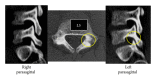

Spondylolysis is reported as a stress fracture of the pars interarticularis with a strong hereditary basis. Three cases of lumbar spondylolysis in juveniles from the same family are reported, and the genetics of the condition are reviewed. The first boy, a 13-year-old soccer player, was diagnosed with terminal stage L5 bilateral spondylolysis with grade 1 slippage. The second boy, a 10-year-old baseball player, had terminal stage right side unilateral spondylolysis. The third boy, also a 10-year-old baseball player, was diagnosed with early stage bilateral L5 spondylolysis. The second and third boys are identical twins, and all three cases exhibited concomitant spina bifida occulta. Lumbar spondylolysis has a strong hereditary basis and is reported to be an autosomal dominant condition.